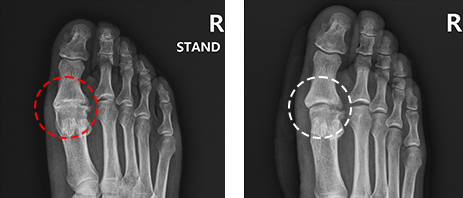

방사선 검사 (X-ray)

X-ray 검사를 통해 중족지 관절 사이의 간격과 골극의 형성을 확인합니다.